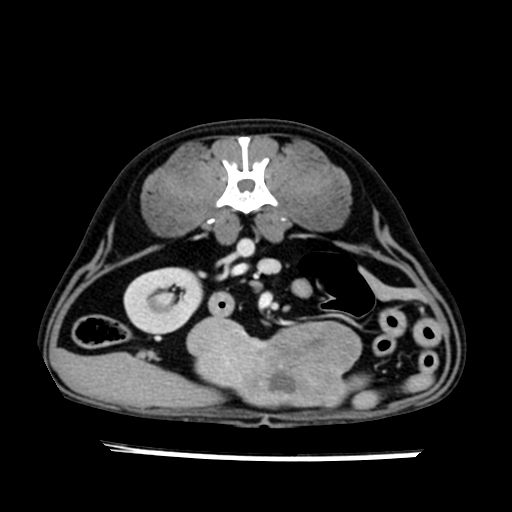

prescritto esame TAC

sequenza immagini limitata al fegato reni e surreni

le immagini ecografiche rispetto alla tac datano circa 7 mesi prima ,le surrenali sono normali nonostante il test acth sia risultato positivo .all’esame TAC dopo diversi mesi risultano aumentate armonicamente nel volume e si individua un forte sospetto di adenoma ipofisario .

sospetto adenoma ipofisario vs. meno probabilmente meningioma della base; intertiziopatia polmonare; lesione espansiva epatica, verosimilmente del lobo laterale sinistro, di sospetta natura neoplastica; lesioni spleniche di natura da definire; iperplasia/ipertrofia delle ghiandole surrenali, bilateralmente; vertebra di transizione del rachide toracico; tenosinovite cronica del muscolo bicipite brachiale di destra.